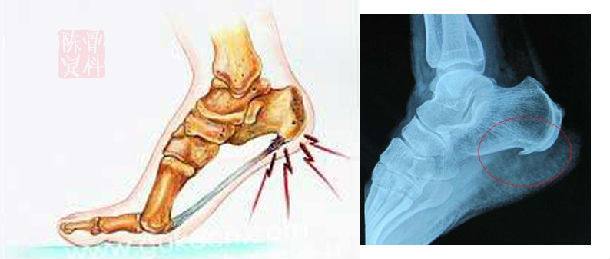

骨刺

在骨科疾病中,大多数都是因为肾气虚导致了骨质疏松,也有的表现为肾气外泄,比如骨质增生,虽然他们都是肾虚,肾气出了问题,但是治法却不一样。

对于大多数肾虚导致的骨质疏松,我们一般使用补肾的方式就可以解决。但是对于骨质增生导致的骨刺就要考虑其他因素了。

为什么会出现骨质增生,长骨刺?

中医认为肾气不足,肾阴虚,肾阳虚都会导致骨质疏松,也会导致骨质增生,两种肾虚疾病的产生都是因为肾气泻的太过,人体不能很好的保存津液,保护好体内的肾气。